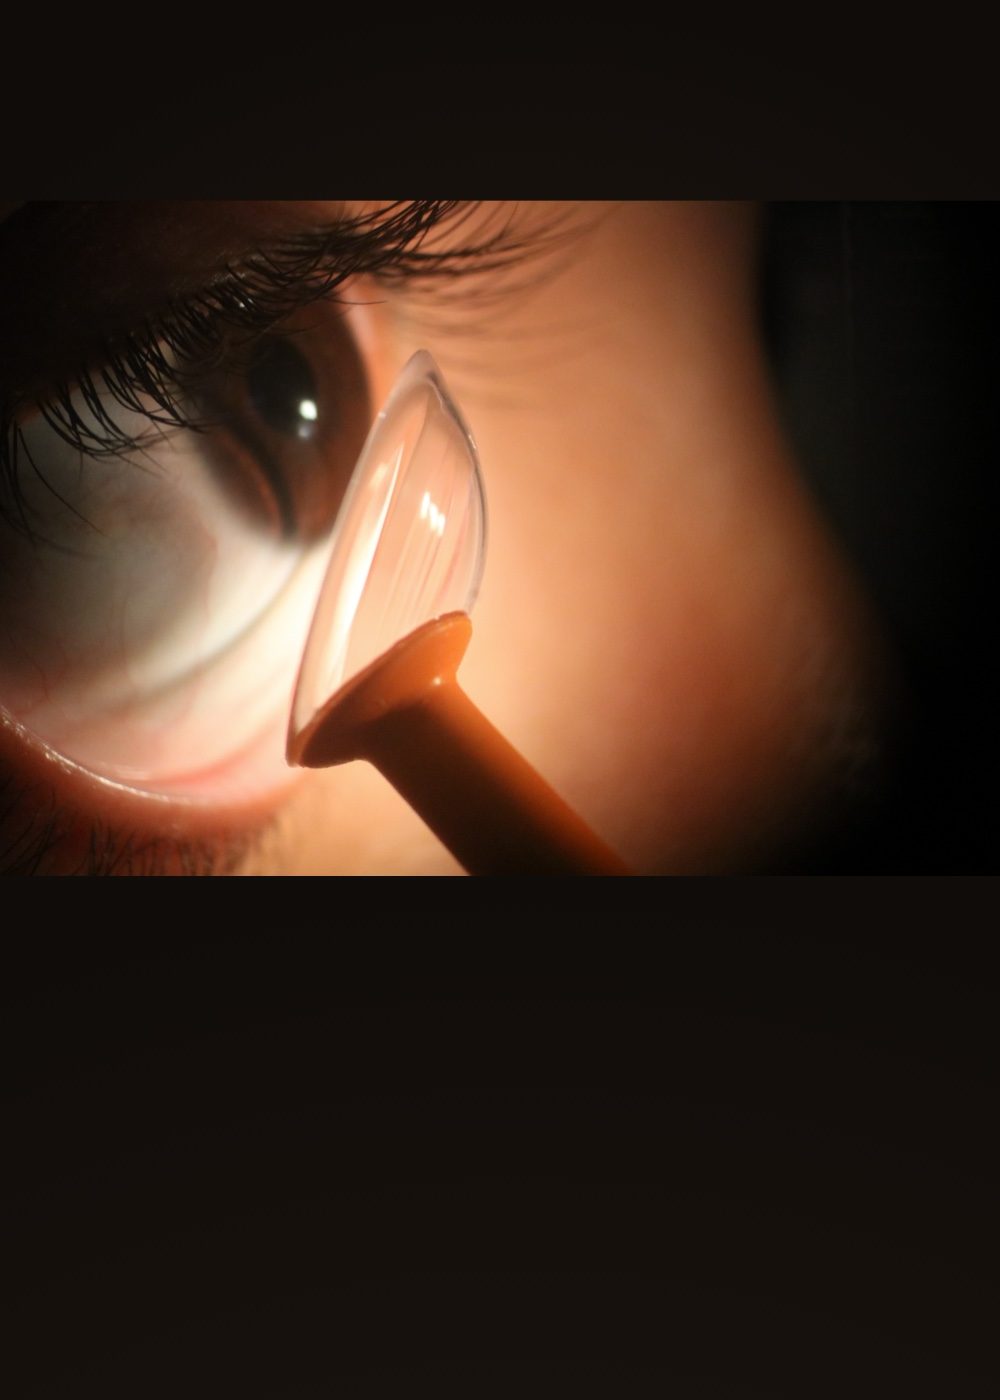

Contactología Especializada

Diseños personalizados de lentes de contacto. ¡Lentes de contacto a tu medida!